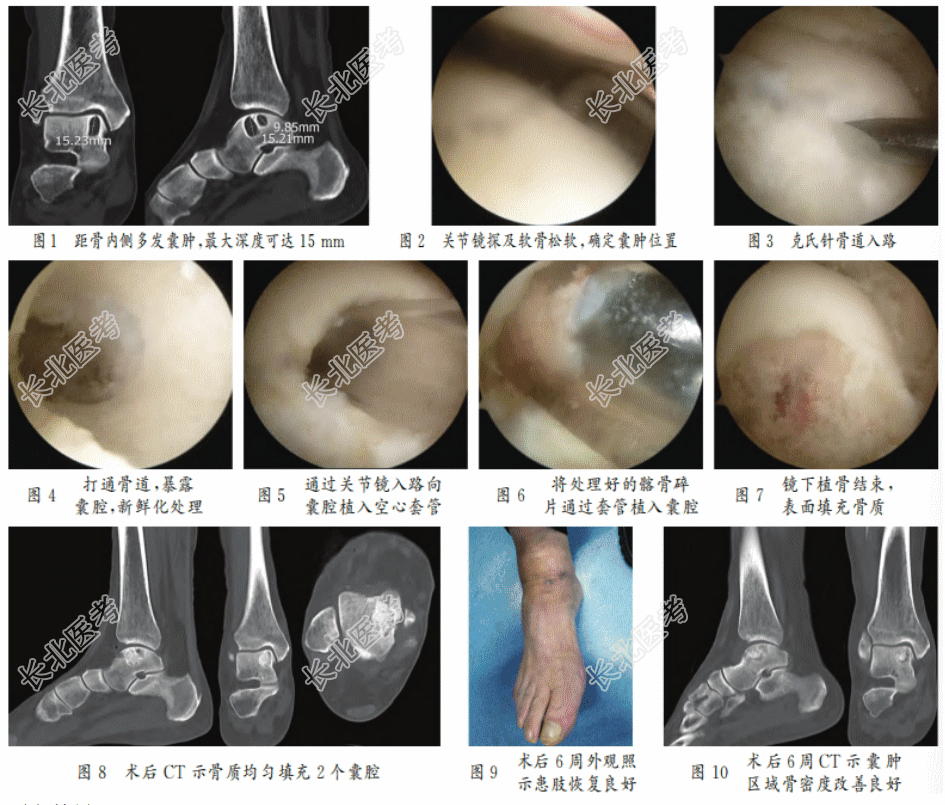

- [材料题] 患者男性,73岁,6年前出现右踝疼痛、伴活动不利,经保守治疗效果不佳,于某日来院就诊。专科检查:右踝轻度肿胀,关节间隙压痛(+),内侧间隙更痛,抽屉实验(±);活动范围受限,跖曲30°,背伸15°,内翻15°,外翻20°;患肢末梢感觉可,趾动及血运可,足背动脉搏动可触及。影像学检查:CT示右踝关节存在间隙,关节面欠平整,距骨内上缘见多发囊状低密度灶,周围骨质密度增高;踝关节边缘可见骨质增生改变,右距骨内上缘囊性灶伴周围密度增高(见图1)。美国足与踝关节协会踝与后足功能评分(AOFAS)52分。于12月入院治疗。

患者麻醉后取仰卧位,右下肢捆扎止血带,右侧髂骨术区及右下肢常规消毒、铺巾/单、覆被,贴护皮膜。延同侧髂嵴做长约5cm切口,逐层切开皮肤、皮下组织,骨膜下剥离,显露髂骨,骨凿凿下大小合适的骨柱并碎片化处理备用,逐层缝合,刀口加压包扎。右下肢驱血后,建立右踝关节前内、前外、前侧关节镜通道,依次探查见踝关节内滑膜增生,距骨前内侧局灶性软骨剥脱,大小约12mm×14mm,软骨损伤区域予以微骨折术处理。以刨刀及射频消融器清理增生的滑膜,局部新鲜化处理后,用探钩确定囊肿位置(见图2)。用克氏针于距骨前内侧穿入暴露囊腔(见图3),可见淡黄色液体流出,扩大骨道后,用刮匙、刨刀清理内侧囊壁,克氏针穿刺囊腔硬化骨壁使之新鲜化(见图4)。将处理好的髂骨碎片经套管植入囊腔并压实平齐周缘骨质(见图5~7)。去除止血带,患者肢端血运良好,置入1根引流管,无菌敷料包扎,术毕。术后CT示囊腔被植骨填充(见图8)。术后6周随访患肢恢复良好(见图9),活动范围跖曲30°、背伸25°、内翻25°、外翻25°,AOFAS评分66分,复查CT示囊肿区域骨密度改善、恢复良好(见图10)。